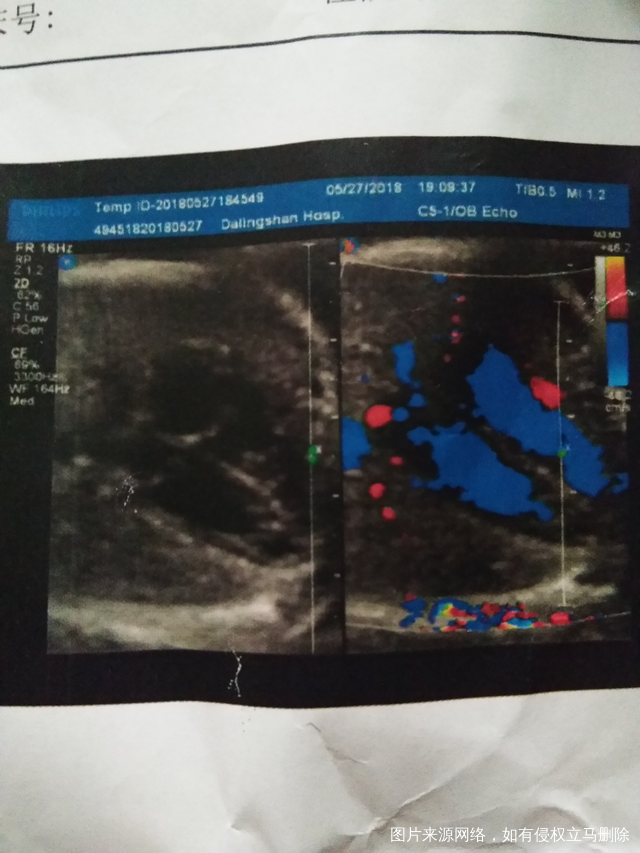

请医生帮忙看下我的糖筛和四维检查结果正常不,谢谢